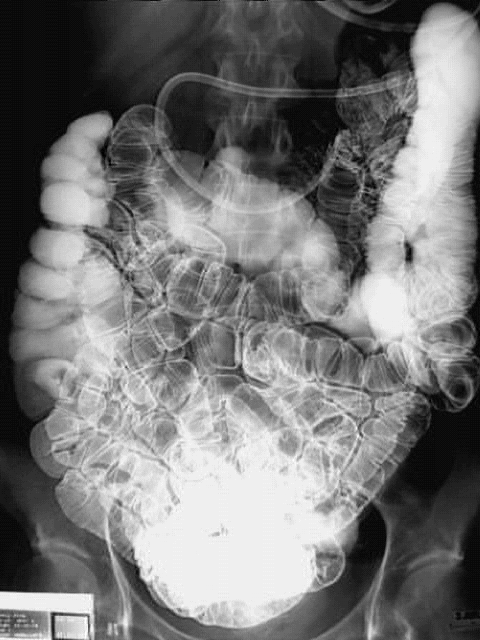

Abdomen- Enteroclysis :